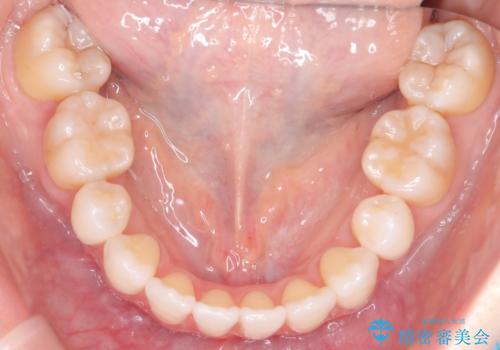

ハーフリンガル矯正|上下4本の抜歯で叢生を改善し、美しい歯並びへ

- 患者様は、歯並びの乱れ(叢生)を整えたいが、前歯の突出感は気にならないとのことで来院されました。診察の結果、全体的な歯列のスペース不足により抜歯が必要と判断。しかし、前歯を大きく下げる必要はなかったため、小臼歯の中でも5番(第二小臼歯)を抜歯する治療計画を立てました。装置は、上顎が舌側(リンガル)、下顎が表側(審美ワイヤー)のハーフリンガル矯正を採用し、目立ちにくさと効率的な歯の移動を両立しました。

抜歯によって歯を並べるためのスペースを確保。その後、ハーフリンガル矯正を用いて、上顎は舌側から、下顎は目立ちにくいワイヤーで歯を誘導し、歯列全体を整えました。治療期間を通じて、噛み合わせのバランスも改善し、機能的にも審美的にも理想的な仕上がりとなりました。患者様からは「目立たずに矯正でき、きれいな歯並びになって嬉しい」とご満足いただきました。